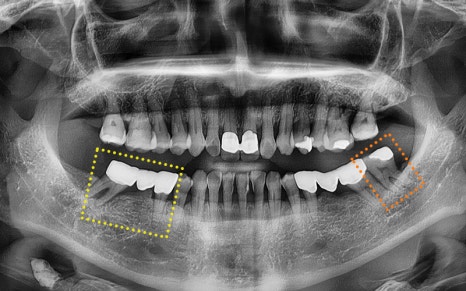

She was experiencing pain in the lower molars on both sides,

and we took a panoramic X-ray

to check the situation in detail.

🦷 Summary of the condition at the time of the visit

✔ The first lower molar on the right

had already been extracted

✔ The second lower molar on the right

was judged to be difficult to preserve due to tooth fracture,

so extraction was decided

✔ The second premolar had a crown already in place,

and it was part of a bridge connected

to the second lower molar

✔ The lower left wisdom tooth

needed extraction due to inflammation

🔍 Treatment plan and process

At Seoul Ob Dental Hospital,

we carefully planned treatment

while considering the patient’s age,

overall health, and treatment burden.

🦷 Final plan

✔ Lower left wisdom tooth

ㅡ> Immediate extraction due to signs of infection

✔ Existing bridge on the lower right

ㅡ> Plan for removal, extraction, and implant placement